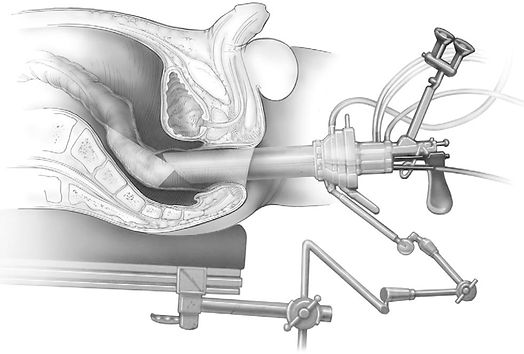

Görsel 1: Rektum tümörü ve incelenmesi.(a) Operasyon öncesi tümör T1.(b) TEM ameliyatı sonrası takip MR. (c) Endoskopik inceleme.(d) PET / CT inceleme.Transanal endoskopik mikrocerrahi, 1980’lerin başında Gehard Buess ve arkadaşları tarafından geliştirilerek cerrahların kullanımına sunuldu. İlk defa Almanya’da geliştirilen TEM, bugün tüm dünyada geleneksel transanal ve abdominal rektal rezeksiyon yöntemlerinin uygulanışına yeni bir yaklaşım imkânı sağlıyor. TEM günümüzde, minimal invaziv bir yöntem olmasıyla ve cerrahi açıdan sağladığı olanaklarla mortaliteyle daha fazla ilişkili olan “total mesorectal excision” (TME) yöntemine alternatif olmuş durumda. TEM yöntemi, 4 farklı parça içeren bir sistemin alanında uzman bir cerrah tarafından kullanımıyla lenf nodlarını eksize etmeden tümörün çıkarılması esasına dayanıyor. Tüm rektum kanseri vakalarında kullanımı uygun olmayan bu yöntem, vakaların TEM’e uygunluğunun seçimiyle başlıyor. Ameliyatta lezyon yerleşimine göre hastaya uygun pozisyon verilmesinin ardından ilk olarak rektum içine rectoscope yerleştirilip sonrasındaysa klasik yöntemlerle lezyon çıkarılıyor. Ameliyatta önce tümör tanımlanıyor ve tümör çevresinde yeterli miktarda bir rektal duvarın tam kalınlıkta kesimi yapılıyor. Cerrah, operasyon boyunca alanının 6 katı büyütme oranı ve 3 boyutlu bir görüntü sağlayan binoküler stereoskopik mercek yardımıyla işlemleri yürütüyor. Örnek rezeke ediliyor, ardından rektum duvarında oluşan defekt dikişlerle kapatılıyor. Bu dikişlerdeyse geleneksel laparoskopik dikiş yerine cerrahi klipsler ve metal boncukların kullanımı cerraha kolaylık sağlıyor. Bu yöntemin dezavantajlarına bakıldığında, lenf nodlarıyla yayılım gösteren kanserlere karşı yeterli etkinlik gösterememesi ve yüksek maliyeti uygulanımını azaltan etkenler olarak gözüküyor. TEM’e en uygun tip, T1 rektal kanserler olarak kabul edilse de seçilmiş T2 N0 rektal kanserler için de sonrasında TEM uygulanan neoadjuvan tedavinin onkolojik sonuçları ümit verici durumda ancak bu yaklaşım henüz değerlendirme aşamasında ve günümüzde klinik çalışmalarla sınırlı tutuluyor. TEM’in diğer kısıtlaması olan maliyeti de TEM platformunun özel alet ve masalarının satın alınmasının yanı sıra TEM insüflasyonu için gerekli olan tek kullanımlık ekipmanın sürekli değişim maliyetleri yüzünden ortaya çıkıyor. Yine de asıl maliyet ilk satın alımda gerçekleştiği için bu yöntemin kullanıldığı, çokça vaka gelen merkezlerde genel maliyetin TEM ile düştüğü görülüyor.

Görsel 2: TEM cihazı ve kullanımı.TEM uygulanması sonrası adenoma nüks oranı %0 ile %16 arasında değişiyor. Bunun yanı sıra TEM, mortaliteyi azaltıyor ve hastalara daha hızlı bir iyileşme süreci sunuyor. Tüm bunlar gelecekte TEM’in kullanımının dünya genelinde daha fazla yaygınlaşacağının ve belki de bir gün rektum kanserinin primer cerrahi müdahale aracı olacağının göstergeleri olsa da farklı yöntemler de bu değişime eşlik ediyor. Bunların başında gelen ve KTÜ Tıp Fakültesi Genel Cerrahi Anabilim Dalında da sıklıkla kullanılan “transanal minimally invasive surgery” (TAMIS) yönteminde, TEM’den farklı olarak tek bir aletin insizyonu operasyon için yeterli oluyor. Özellikle erken evre kanserlerinde uygulanan bu yöntem, TEM’in getirdiği avantajları daha efektif bir şekilde uygulamaya imkân sağlıyor.Kanser gün geçtikçe tedavisi olmayan bir hastalık olmaktan uzaklaşıyor. Teknoloji de bizlere bu yolculukta yardımcı olmaya devam ediyor. Kim bilir, şimdiden göz kırptığımız yenilikler ışığında, belki de ileride kansersiz bir dünyaya göz açarız.